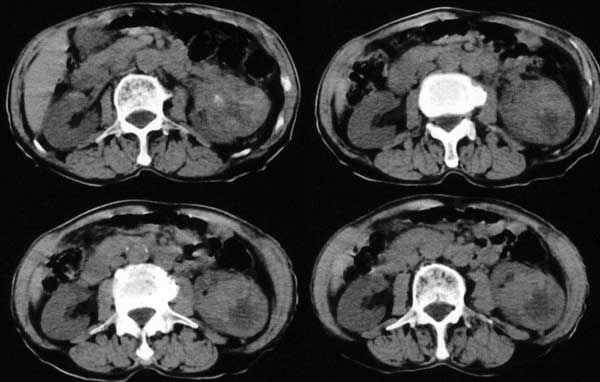

附肾脏平扫及增强片

支持肺内,椎体,肋骨,腹膜后淋巴转移.

肺及胸膜下多发结节影,胸椎及附件、肋骨破坏支持转移癌。气管内结节影支持痰核。肾脏ct应该是术前的吧?左肾内亦见一低密度灶,另外胰腺好像也不规则。不知术后结果如何?

左侧肾癌,腹膜后淋巴转移,肺及胸椎转移,右肾转移可能,气管内痰栓可能[壁可见]

左侧肾癌伴腹膜后淋巴结、胸椎、双肺内转移。